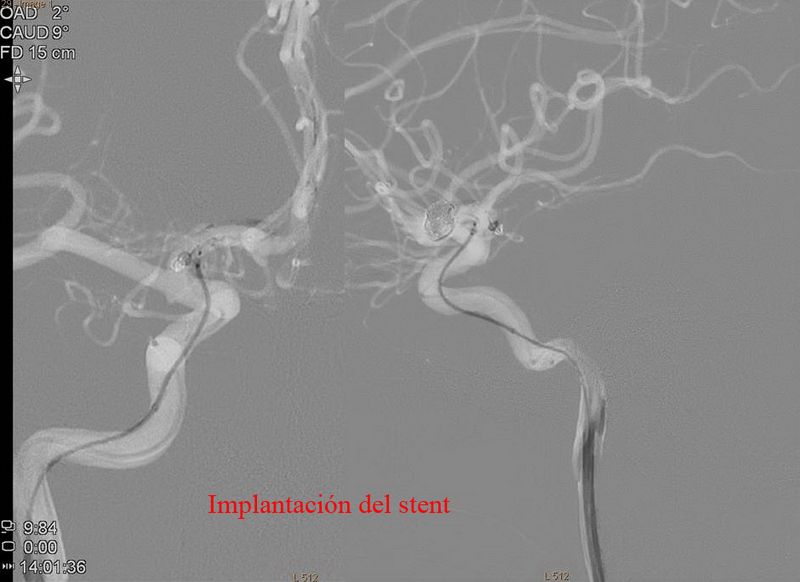

Aneurisma de arteria comunicante anterior